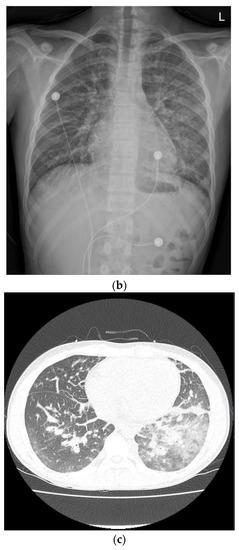

On the second day of hospitalization, he complained of dizziness, chest discomfort, and dyspnea before magnetic resonance (MR) enterography and endoscopy were performed. Vital signs were unstable; blood pressure was 80/60 mmHg, heart rate was 128 beats/min, respiratory rate was 30/min, body temperature was 36.4 °C, and oxygen saturation was 80%. Arterial blood gas analysis revealed a pH of 7.5, pCO2 of 31, and HCO3 of 24.2. Chest radiography and CT revealed pulmonary edema and cardiomegaly (Figure 1).

Figure 1.

Compared with the chest radiography (a) at the time of admission, the chest radiography (b) and low-dose chest computed tomography (c) performed on the second day of hospitalization revealed pulmonary edema and cardiomegaly findings (b).